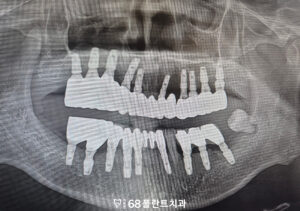

<상악동거상술 및 임플란트 진행>

먼저 발치가 필요한 치아들은 모두 정리한 후,

상악 구치부의 부족한 골을 보완하기 위해

상악동거상술을 시행하였으며,

이후 안정적인 골 형성이 확인된 뒤

임플란트를 식립하는 순서로

치료를 진행하였습니다.

그리고 임플란트와 이식한 뼈가

충분히 유착되어 안정화된 것을 확인한 후,

최종 보철 치료를 진행하여

기능적·심미적 회복을 이루며

치료를 마무리하였습니다.

<타원 임플란트 보철 진행>

또한 타원에서 임플란트가 식립된 부위도

현재 상태를 면밀히 평가한 후,

주변 조직과의 안정성을 확인하였으며,

이상 소견이 없는 것을 확인한 뒤

보철 치료를 이어서 진행하였습니다.

위쪽 임플란트 보철에 맞춰 교합을 조정하여

위, 아래의 균형을 맞추고,

전체적인 저작 시 힘이 고르게

분산될 수 있도록 했는데요.

이를 통해 해당 부위 역시

정상적인 저작 기능을

회복할 수 있도록 하였습니다.

그리고 사랑니까지 전부 발치한 후

전체적인 치료를 마무리할 수 있었습니다.